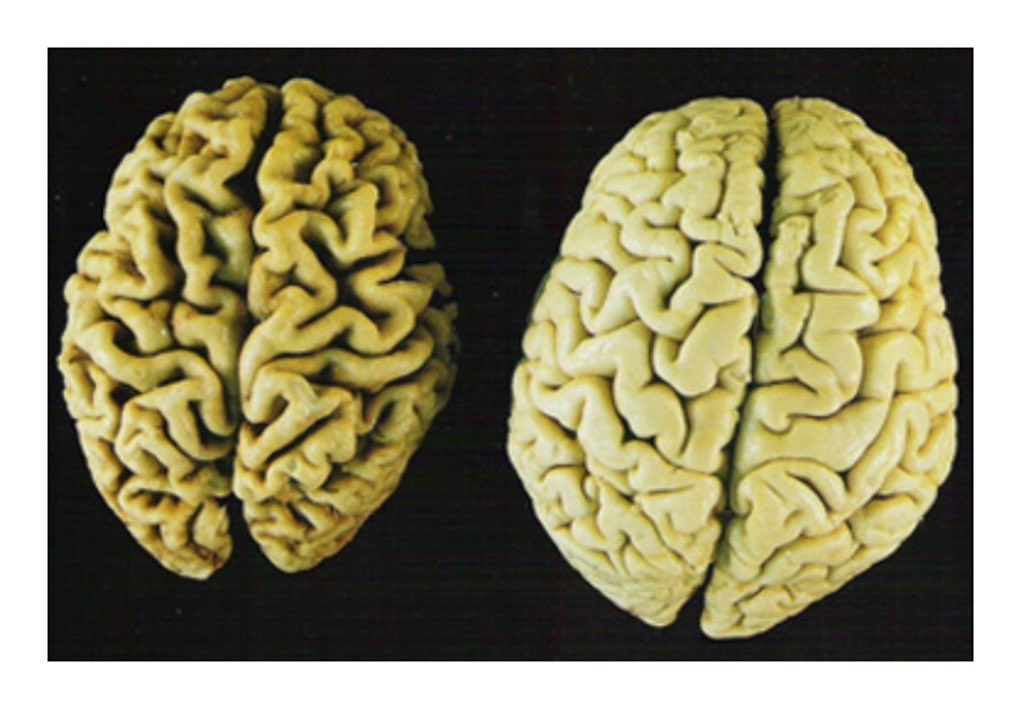

عادةً مايتضمن التشخيص اختباراً بدنياً يتبعه اختباراتٍ معينةٍ،ويظهر ضمور الدماغ في عمليات مسح تصوير الدماغ منها:

*الرنين المغناطيسي(MRI)الذي يخلق صوراً دماغيةً عالية الدقة للتشخيص